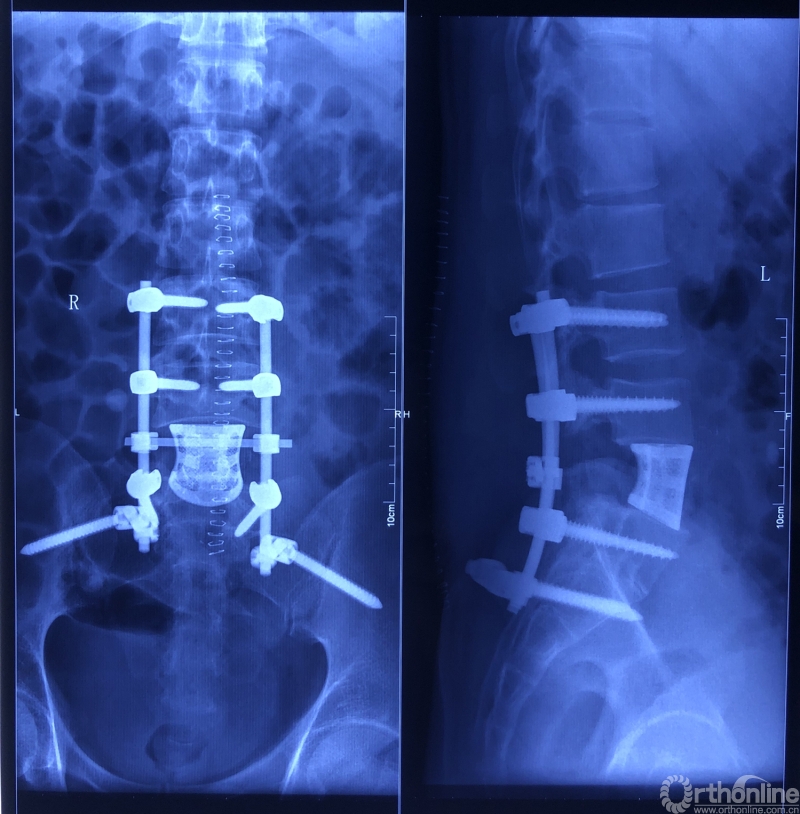

在三大技术的保驾护航以及李锋教授高超的手术技巧下,手术顺利结束。肿瘤和被侵蚀的椎体被切除,人工椎体被两根矫形棒和八颗螺钉稳稳固定在脊椎缺口处,脊柱结构重建。与传统手术方案相比,患者创伤减少,软组织及血管、神经等破坏更少,肿瘤清除更彻底,局部肿瘤复发率更低。术后患者生命体征平稳,安返病房。病灶已送检,将根据病检结果指导进一步的治疗。目前,病人神志清醒、腰痛缓解、恢复良好。

术后X线片